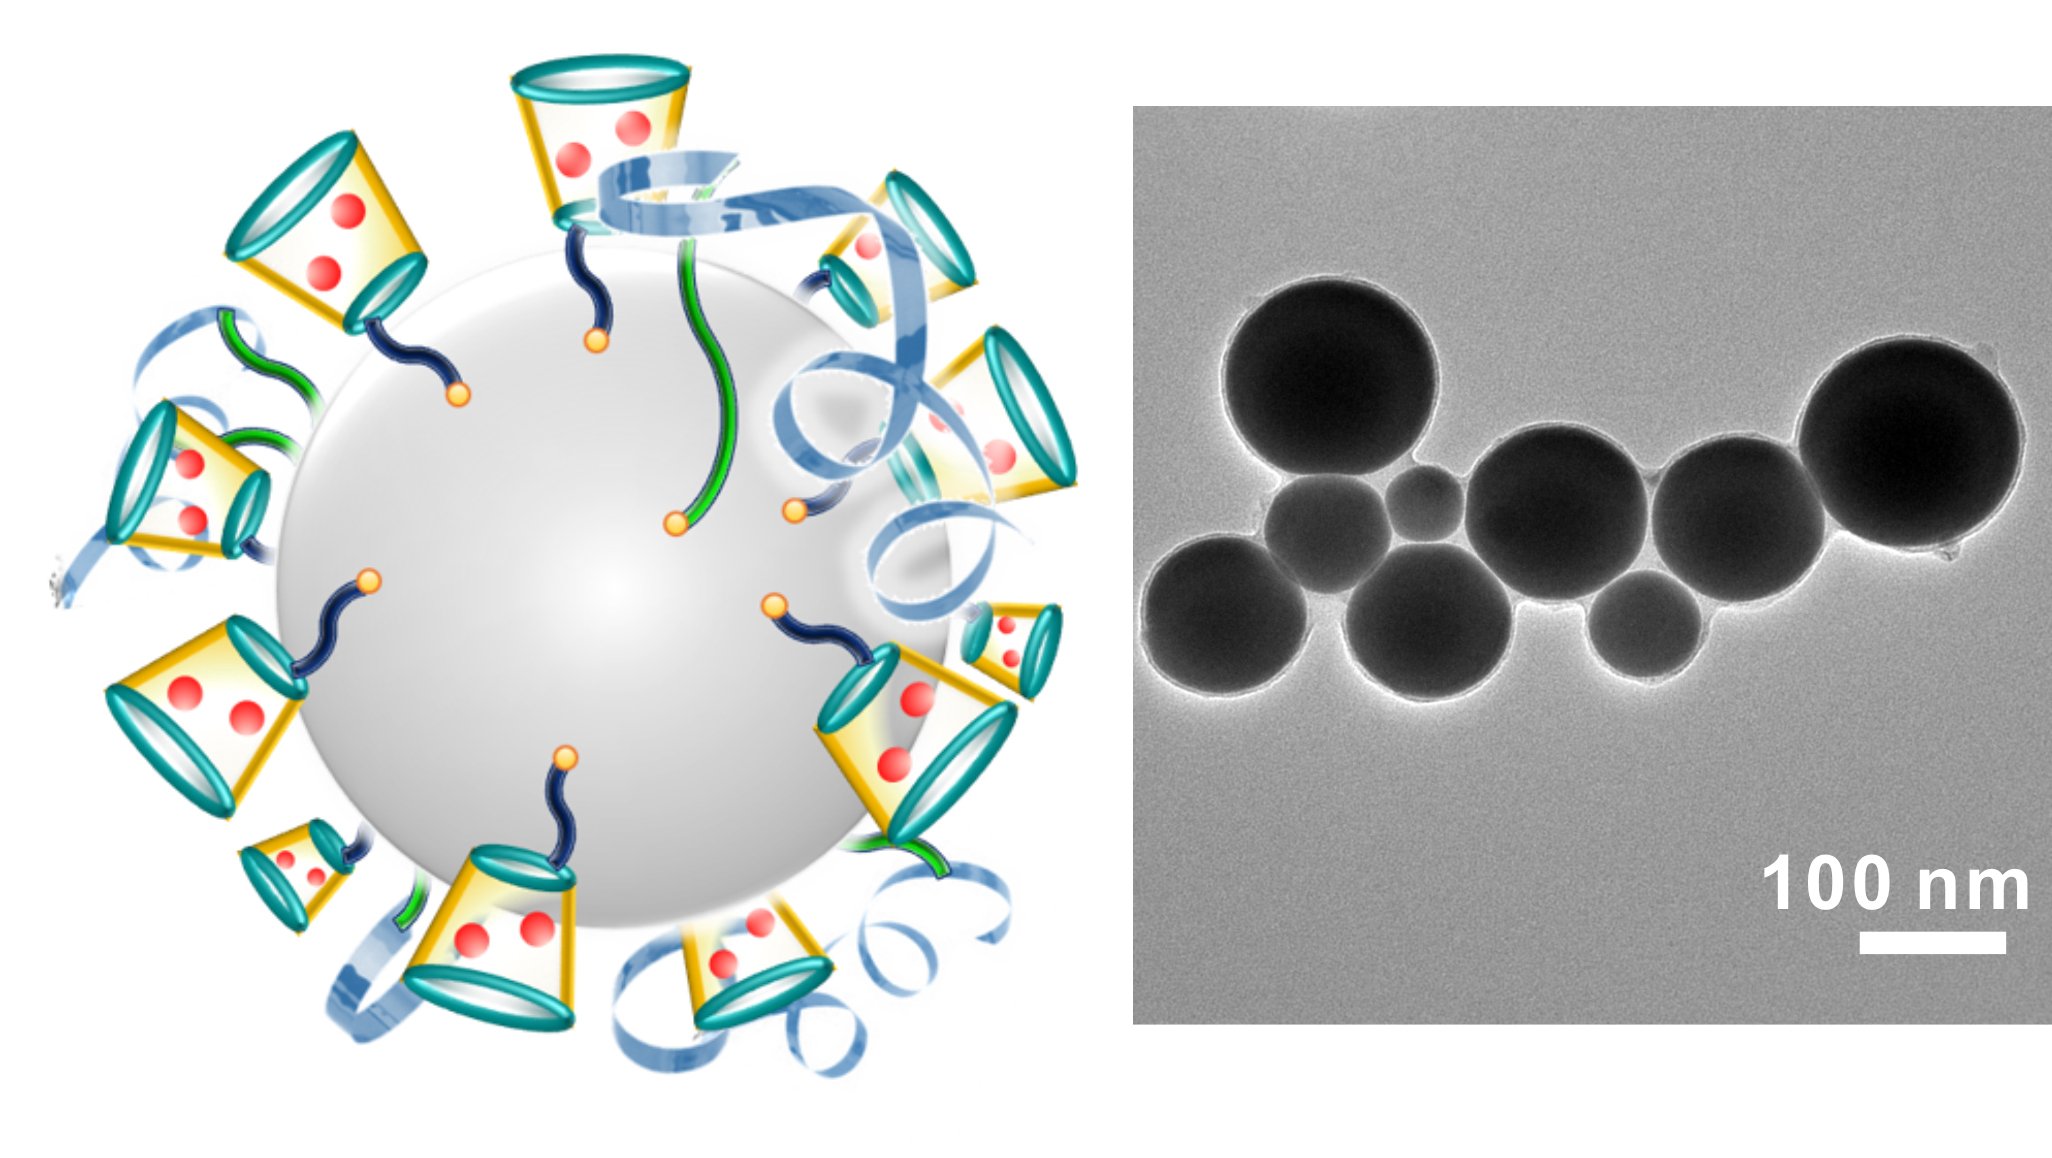

Links ist eine schematische Darstellung der krebsbekämpfenden Nanopartikel zu sehen. Das Chemotherapeutikum Doxorubicin ist in Rot abgebildet. Die rechte Aufnahme zeigt die Nanopartikel durch ein Elektronenmikroskop fotografiert.

Quelle: Yue Lu/North Carolina State University

Die US-Wissenschaftler zerstäuben das Material mit Hilfe von Ultraschall, sodass Partikel mit einem Durchmesser von etwa 100 Nanometern entstehen. Mit Liganden, das sind Moleküle oder Atome, die eine feste Verbindung eingehen, befestigen sie an den Nanoteilchen Doxorubicin, einen Wirkstoff, wie er bei Chemotherapien genutzt wird. Bei dieser Art der Behandlung werden nicht nur die Krebszellen zerstört, sondern auch umliegendes gesundes Gewebe geschädigt.